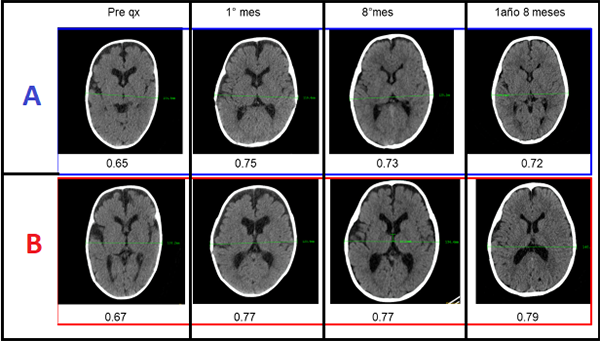

Comparamos los índices cefálicos de ambos. Al año y ocho meses de la cirugía, el índice cefálico del gemelo A fue 0.72 y del B 0.79 (Fig. 19).

El gemelo A tenía un índice cefálico prequirúrgico de 0.65 y el B de 0.67. Es decir que el gemelo A aumentó 0,07 y el B 0,12. Por lo tanto se pudo determinar que la técnica con tracción mediante sutura tuvo mejor resultado.

Si observamos la evolución cronológica de los índices cefálicos de ambos gemelos podemos observar lo siguiente:

El gemelo B muestra mejoras de su IC con el paso del tiempo: 0.77 al mes y 0.79 al año y 8 meses de la cirugía. El gemelo A muestra un comportamiento inverso: al primer mes tiene un IC de 0.75, al octavo mes de 0.73 y al año y 8 meses 0.72 (Fig. 20), siendo éste un valor de IC aceptable.

FIGURA 20: Evolución comparativa de los índices cefálicos de los gemelos. A- Sin tracción. B- Con tracción.